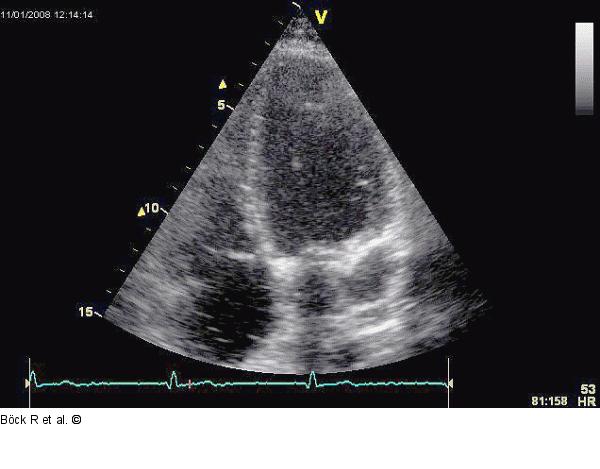

Abbildung 5: Sinus coronarius Kaudal angulierter Vierkammerblick mit Kontrastmittel im Sinus coronarius, dann im rechten Ventrikel. |

Kaudal angulierter Vierkammerblick mit Kontrastmittel im Sinus coronarius, dann im rechten Ventrikel. |